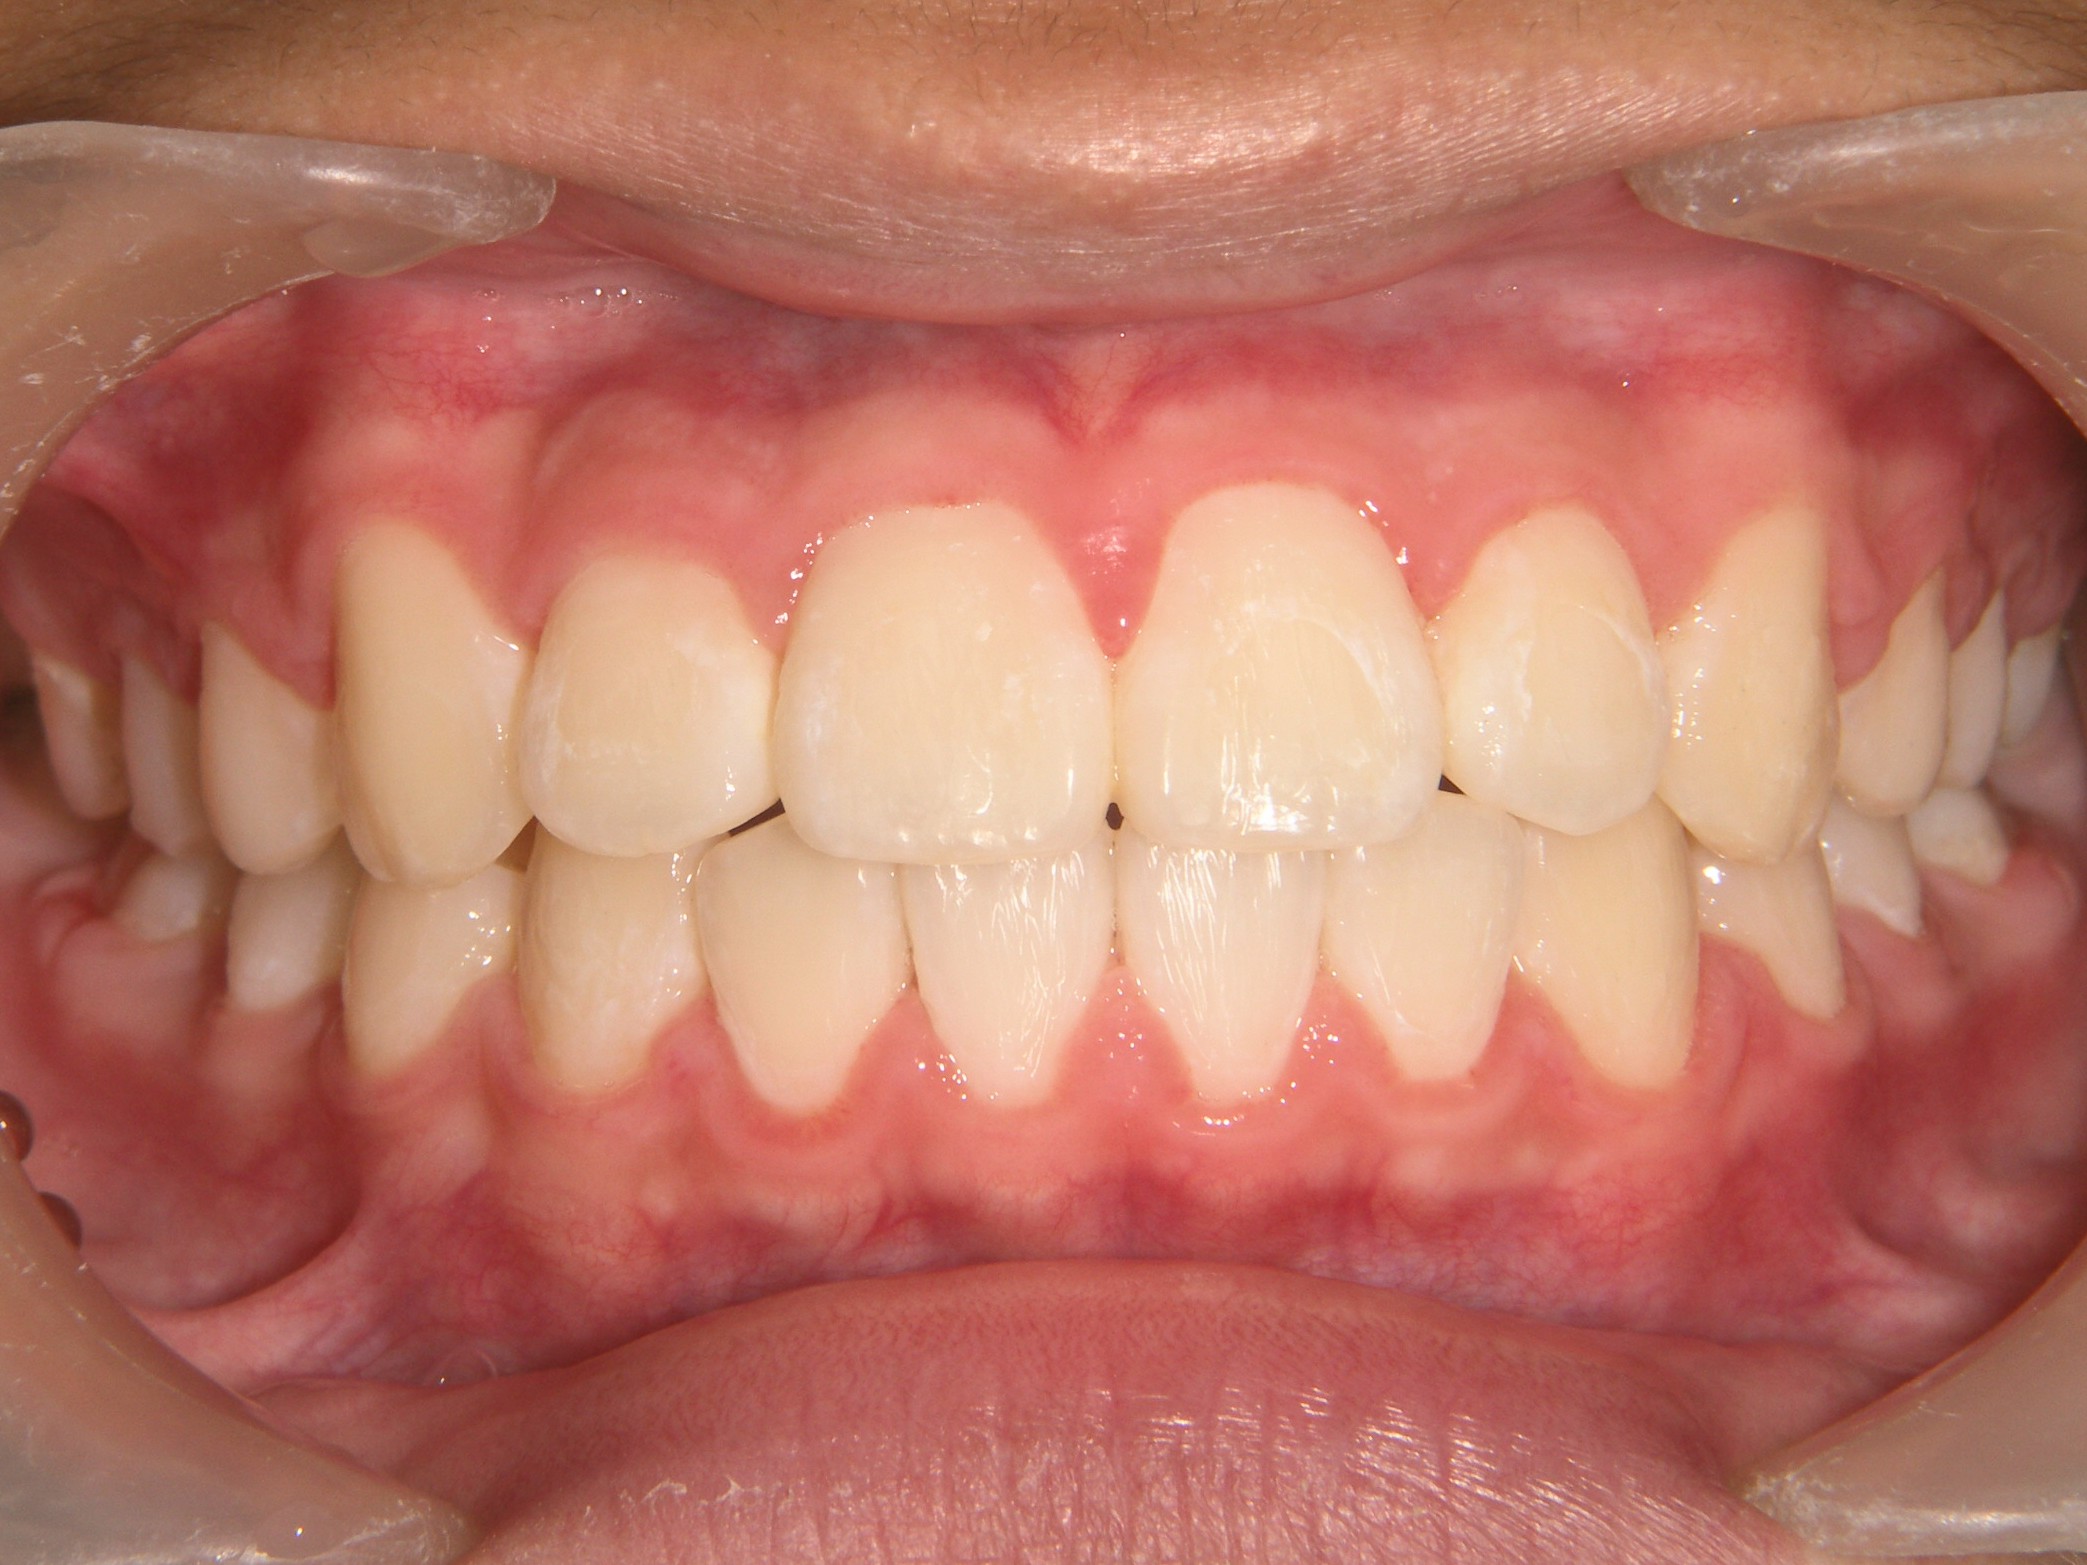

第2期治療開始時

顔貌写真

口腔内写真

開始年齢

13歳

主訴(患者様のお悩み)

残りの歯のデコボコを治したい

診断

上下顎軽度の叢生(上下の歯のデコボコ)

上顎右側犬歯低位(右上の八重歯)

治療方針

非抜歯矯正治療

全体的に装置を装着し、歯のデコボコや咬み合わせを治療

使用装置

表側矯正装置

治療期間の目安:約1年~1年半(保定期間を除いた期間)